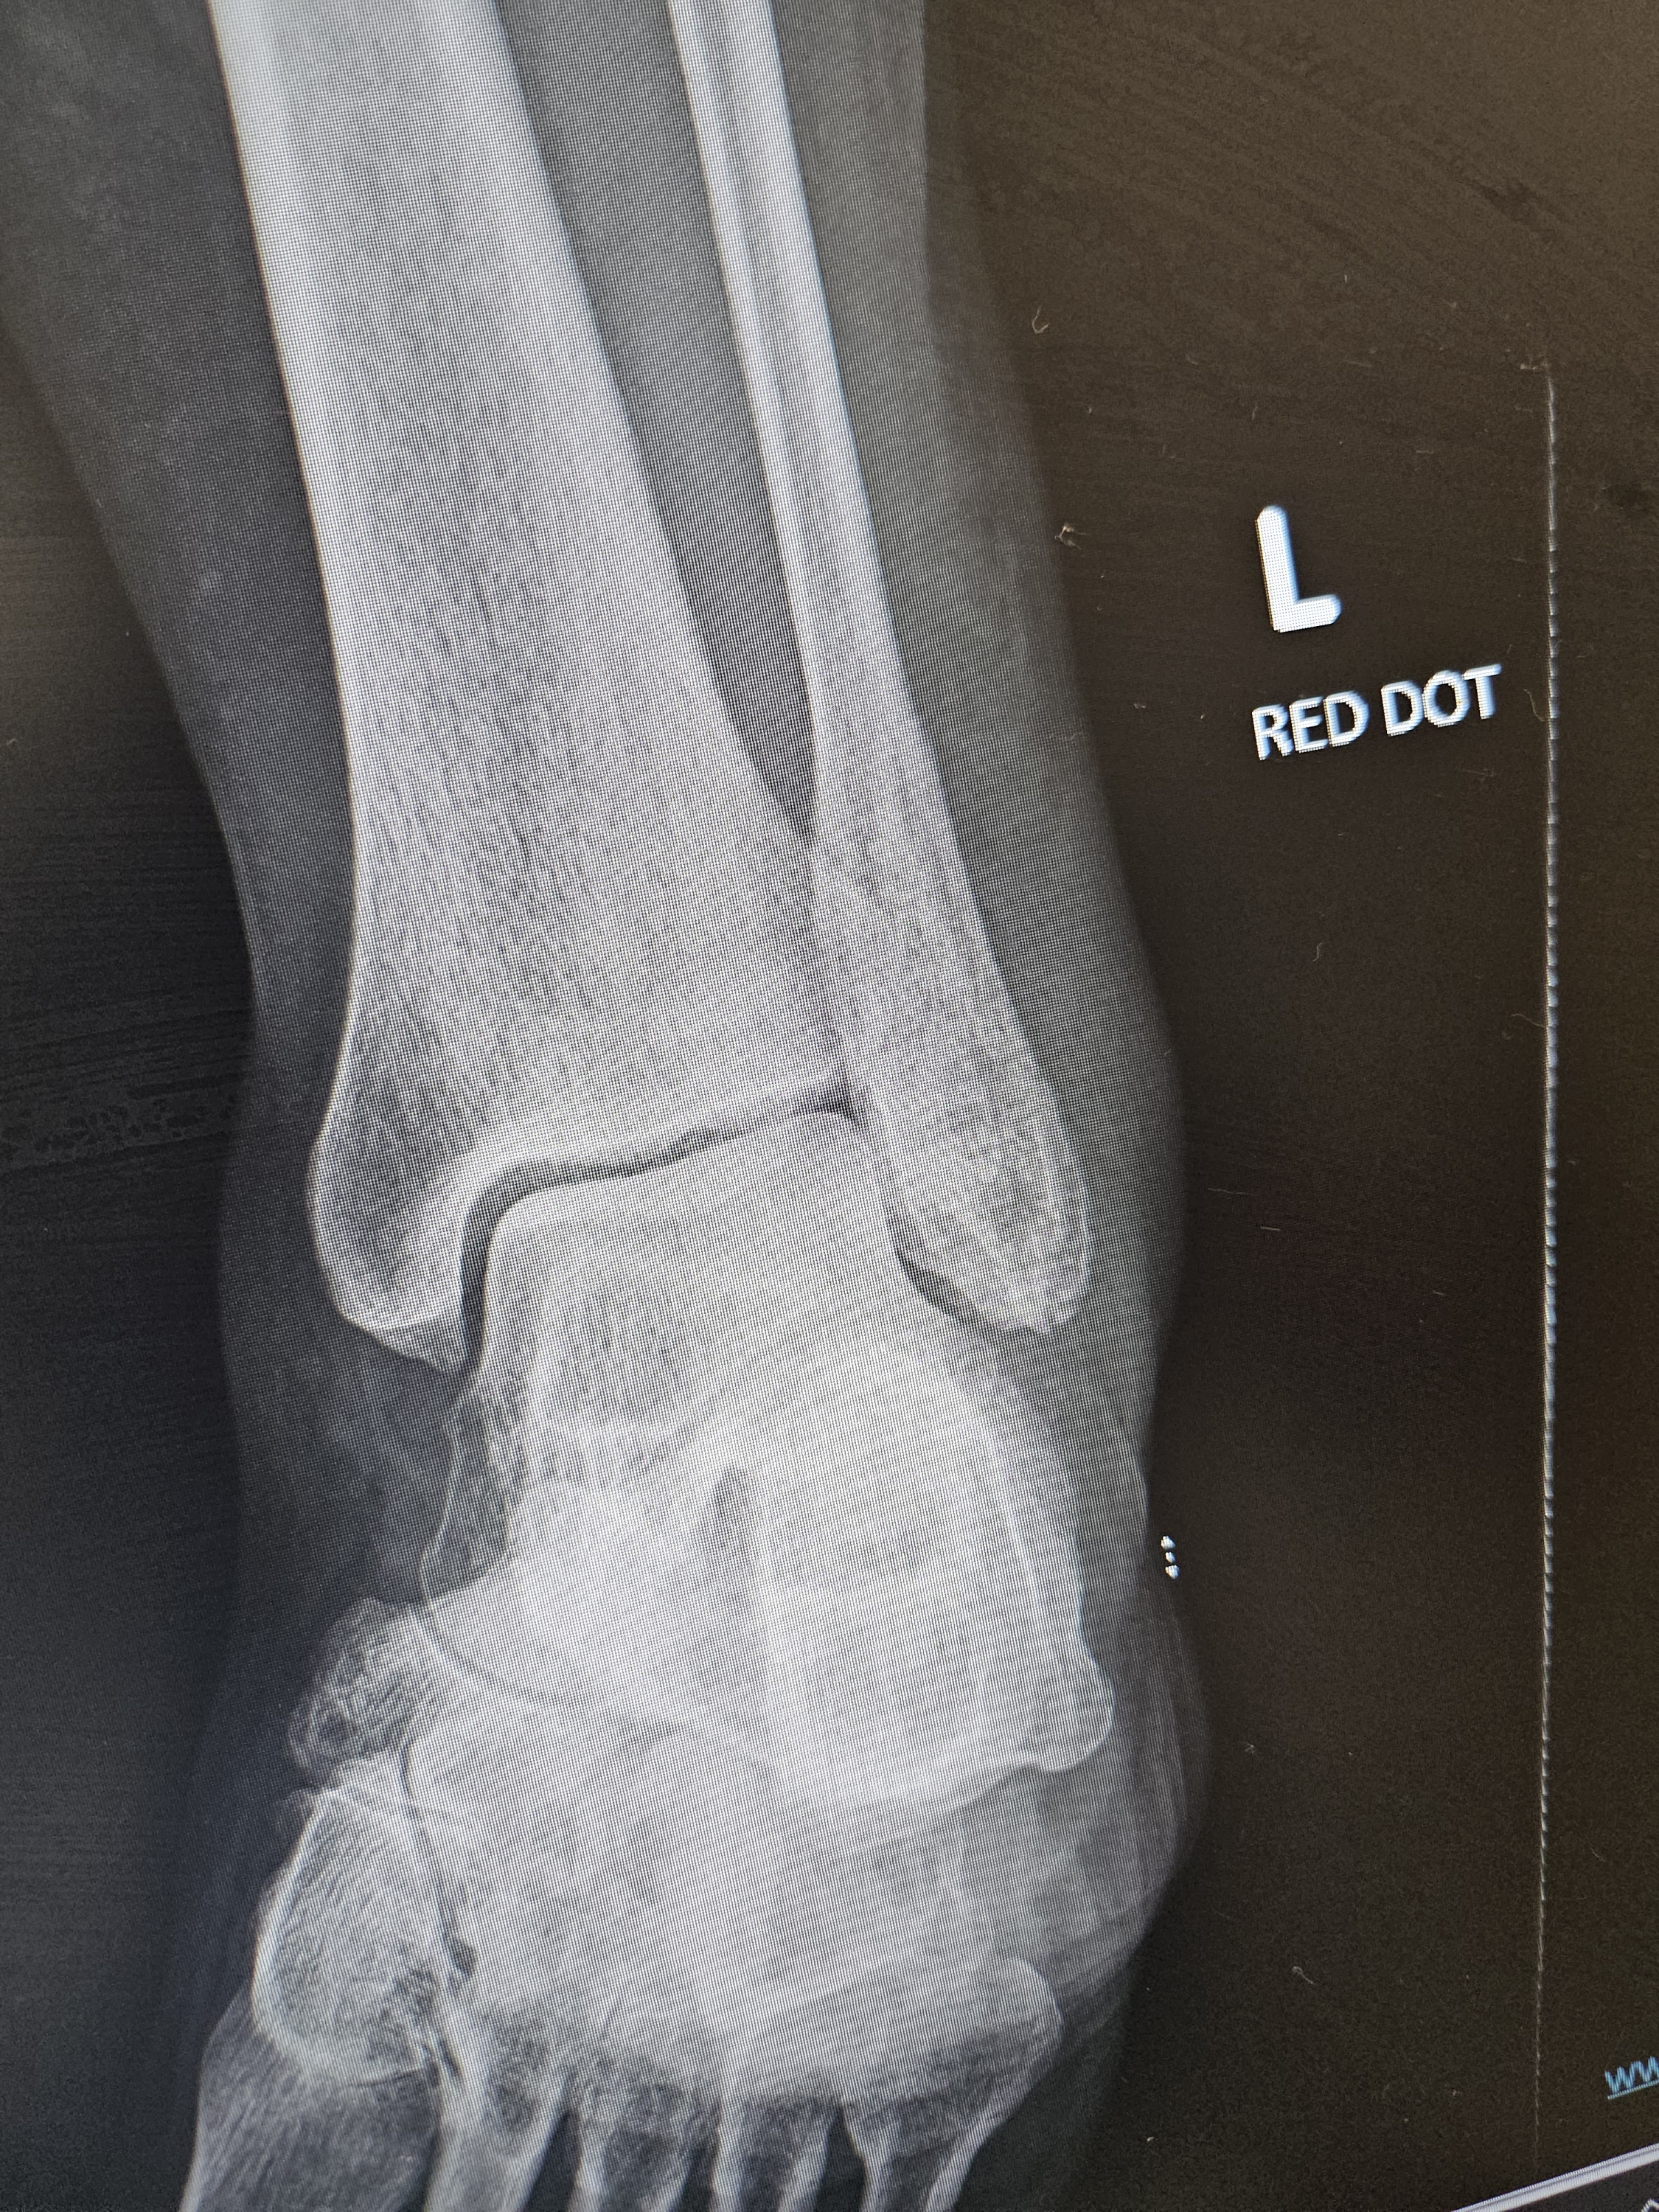

I got bk on bed and reaized my L leg was swelling up badley phoned my daughter to come down as i was in agony phoned ambulance i have broken my left fibula bone at the bottom & also broken near my toes aswell why i was in servre pain 10/10 i have a walking boot been to phyiso and OT R comming to asses the bungalow for OT rails and whatever else they can put up for me to prevent this happening again.